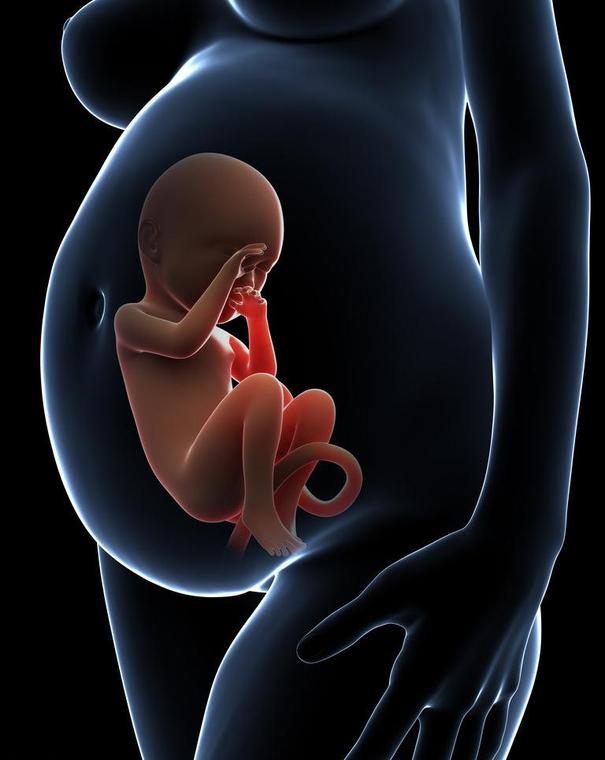

现在随着医学的发达,四维彩超基本已经普及,每个妈妈都希望生下来的宝宝是健康的,那么你知道四维彩超到底是检查了哪些项目呢?这些检查有没有必要呢?下面请让我用图片展示给大家看看。

四维彩超除了能让准父母提前看到宝宝在妈妈肚子里的活动情况,最主要的功能还在于对胎儿进行各种检查,及早发现胎儿生长中出现的问题 ,另外,四维彩超的图象显示比传统B超更清晰、更准确, 能够多方位、多角度地观察宫内胎儿的生长发育情况,为早期诊断胎儿先天性体表畸形和先天性心脏疾病提供准确的科学依据。因此,为了孕妇和胎儿的健康,产检选择做四维彩超检查非常有必要。WX(艾的秘密)